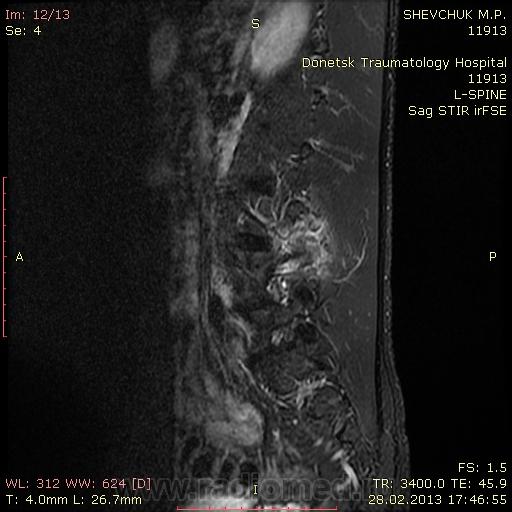

Молодой человек, 21 г. Жалуется на боли  в пояснице слева. Занимался спортом, делал упрожнения с гантелями, с наклоном корпуса влево и вправо, после чего почувствовал боль. На уровне   левого дугоотросчатолого сочленения L4 позвонка спереходом на дужку и тело определяется зона с повышенным МРС. Приледащием мышцы также отечны. Как вы думаете, что это может быть? Не нравится увеличеннное в размерах левое дугоотросчатое сочленение.

Картинки не загрузились, поэтому оценить состояние дугоотростчатого сустава не представляется возможным.Если есть повышение сигнала в режиме с жироподавлением, то возможен перелом.Если по Т1, Т2 , то жировая дистрофия либо гемангиома.

Жировая дегенерация ножки, следствие множественных перегрузок; сплошь и рядом у спортсменов, строителей и к ним причисляемых. Для перестраховки можно добавить МСКТ - увидеть/не увидеть старый перелом.

Очень напоминает абсцесс либо разрыв  мышцы слева.Короналы Т2 хорошо бы посмотреть.

Короналы, к сожалению не делала. Тоже думала о травматическом повреджении паравертебральных мышц слева. Бесспокоюсь на счет перелома: не патологический ли он случайно?